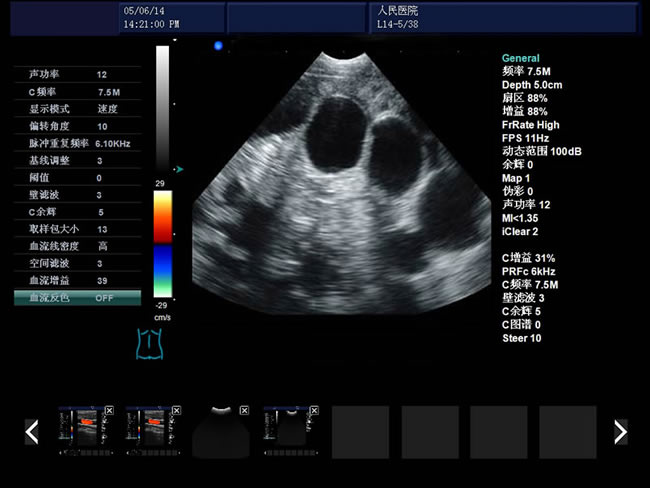

• S8彩色多普勒獸用超聲診斷儀是徐州市大為電子設(shè)備有限公司推出的一款全新的彩色超聲診斷儀器。

適用范圍:B超機(jī)產(chǎn)品性能

高集成數(shù)字式彩色多普勒技術(shù)

寬頻探頭,頻率范圍從2.0MHz到10.0MHz

1、檢查母豬的空懷,降低無效飼養(yǎng)的功效早已深入人心

2、用B超監(jiān)測可及早準(zhǔn)確掌握妊娠母豬頭數(shù),較高的早期妊娠診斷準(zhǔn)確率較好的保證了均衡生產(chǎn)

3、探查時(shí)間短、無應(yīng)激、準(zhǔn)確率高,而且產(chǎn)生巨大的生產(chǎn)應(yīng)用價(jià)值